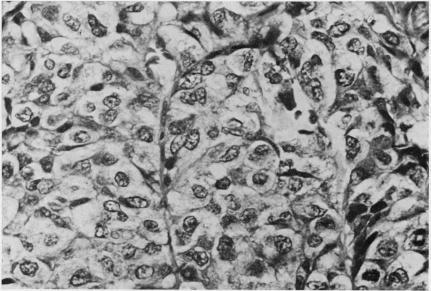

In 9 years in Kenya, 34 examples of primary liver cancer wer diagnosed in patients in the first two decades of life. This represents 4.7% of all liver cancers during this period. The larger proportion (29) were hepatocellular carcinoma. In the second decade, there was a notable association with macronodular cirrhosis. Analogy with experimental work suggests that cells in mitotic cycle may be more vulnerable to the effect of environmental carcinogens. Five examples of hepatoblastoma were identified at ages from 2 months to 14 years; none showed the features of "mixed" tumours. The ratio of hepatoblastoma to hepatocellular carcinoma was the reverse of that found in other large series of juvenile hepatic tumours. The histopathological features of these tumours are described and problems of their classification are discussed.

在肯尼亚的9年里,34例原发性肝癌在20岁之前的患者中被诊断出来。这占该时期所有肝癌的4.7%。其中较大比例(29例)为肝细胞癌。在第二个十年中,与大结节性肝硬化有显著关联。与实验工作的类比表明,处于有丝分裂周期的细胞可能更容易受到环境致癌物的影响。在2个月至14岁的年龄段中发现了5例肝母细胞瘤;均未表现出“混合”肿瘤的特征。肝母细胞瘤与肝细胞癌的比例与其他大量青少年肝脏肿瘤系列中的情况相反。描述了这些肿瘤的组织病理学特征,并讨论了它们的分类问题。